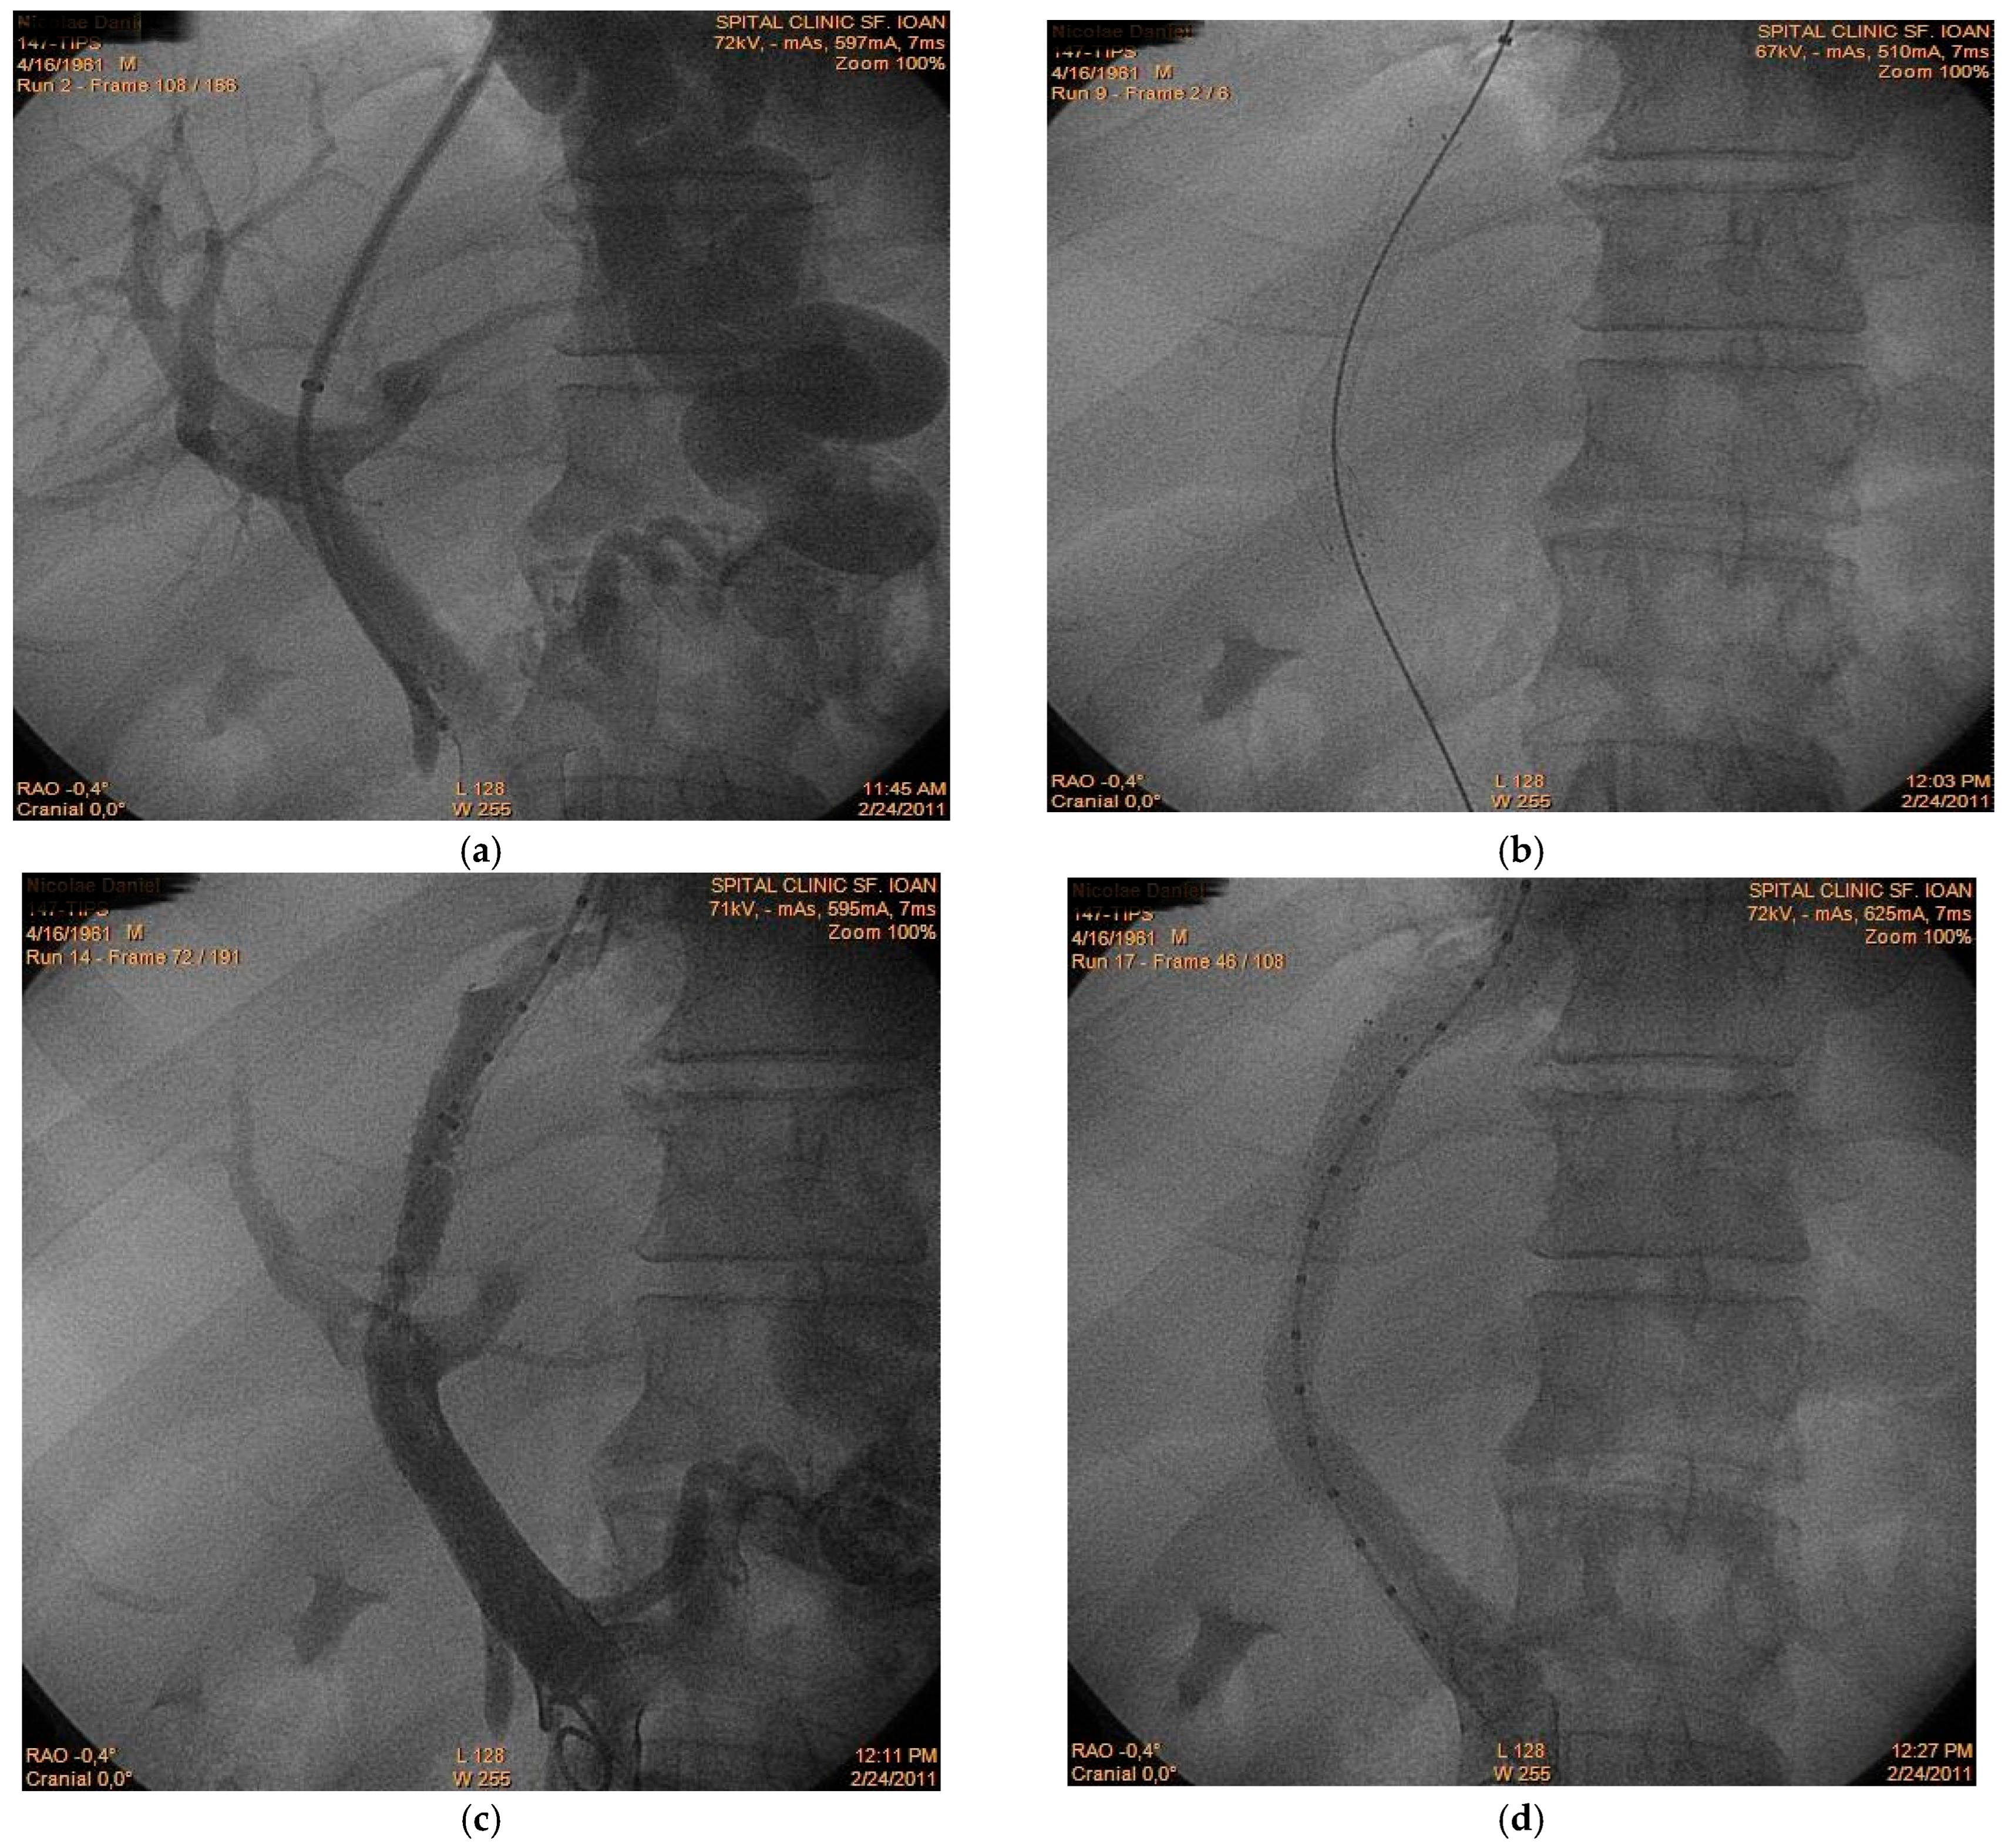

A 56-year-old male patient with alcoholic liver cirrhosis was admitted for acute variceal bleeding refractory to endoscopic therapy. Within the following 2 months, the patient experienced two episodes of rebleeding; therefore, the hemorrhage was considered refractory to standard therapy. The decision was made to perform transjugular intrahepatic portosystemic shunt (TIPS) placement as secondary prophylaxis. However, immediately after intrahepatic tract creation (Figure 1a), acute thrombus formation was observed within the main portal vein (Figure 1b,c), suggesting intraprocedural de novo thrombosis rather than embolization of a pre-existing clot. Prompt placement of a second stent restored the portal flow (Figure 1d) and the patient had a favorable outcome. This case illustrates a rare but clinically significant phenomenon: rapid intraprocedural portal vein thrombosis. While shunt dysfunction and delayed thrombosis are recognized complications, acute thrombus formation during tract creation is scarcely reported. The observation supports the hypothesis that endothelial trauma and abrupt hemodynamic changes may trigger immediate thrombogenesis in a prothrombotic cirrhotic milieu. Awareness of this possibility is essential, as rapid recognition and mechanical correction may prevent shunt failure and early clinical deterioration.

Figure 1.

TIPS-related acute portal vein thrombosis (a) Initial portal venography demonstrating intrahepatic tract creation; (b) First stent placement; (c) Intraprocedural acute thrombus formation between portal and suprahepatic vein; (d) Post-stent restoration of flow following second stent placement.